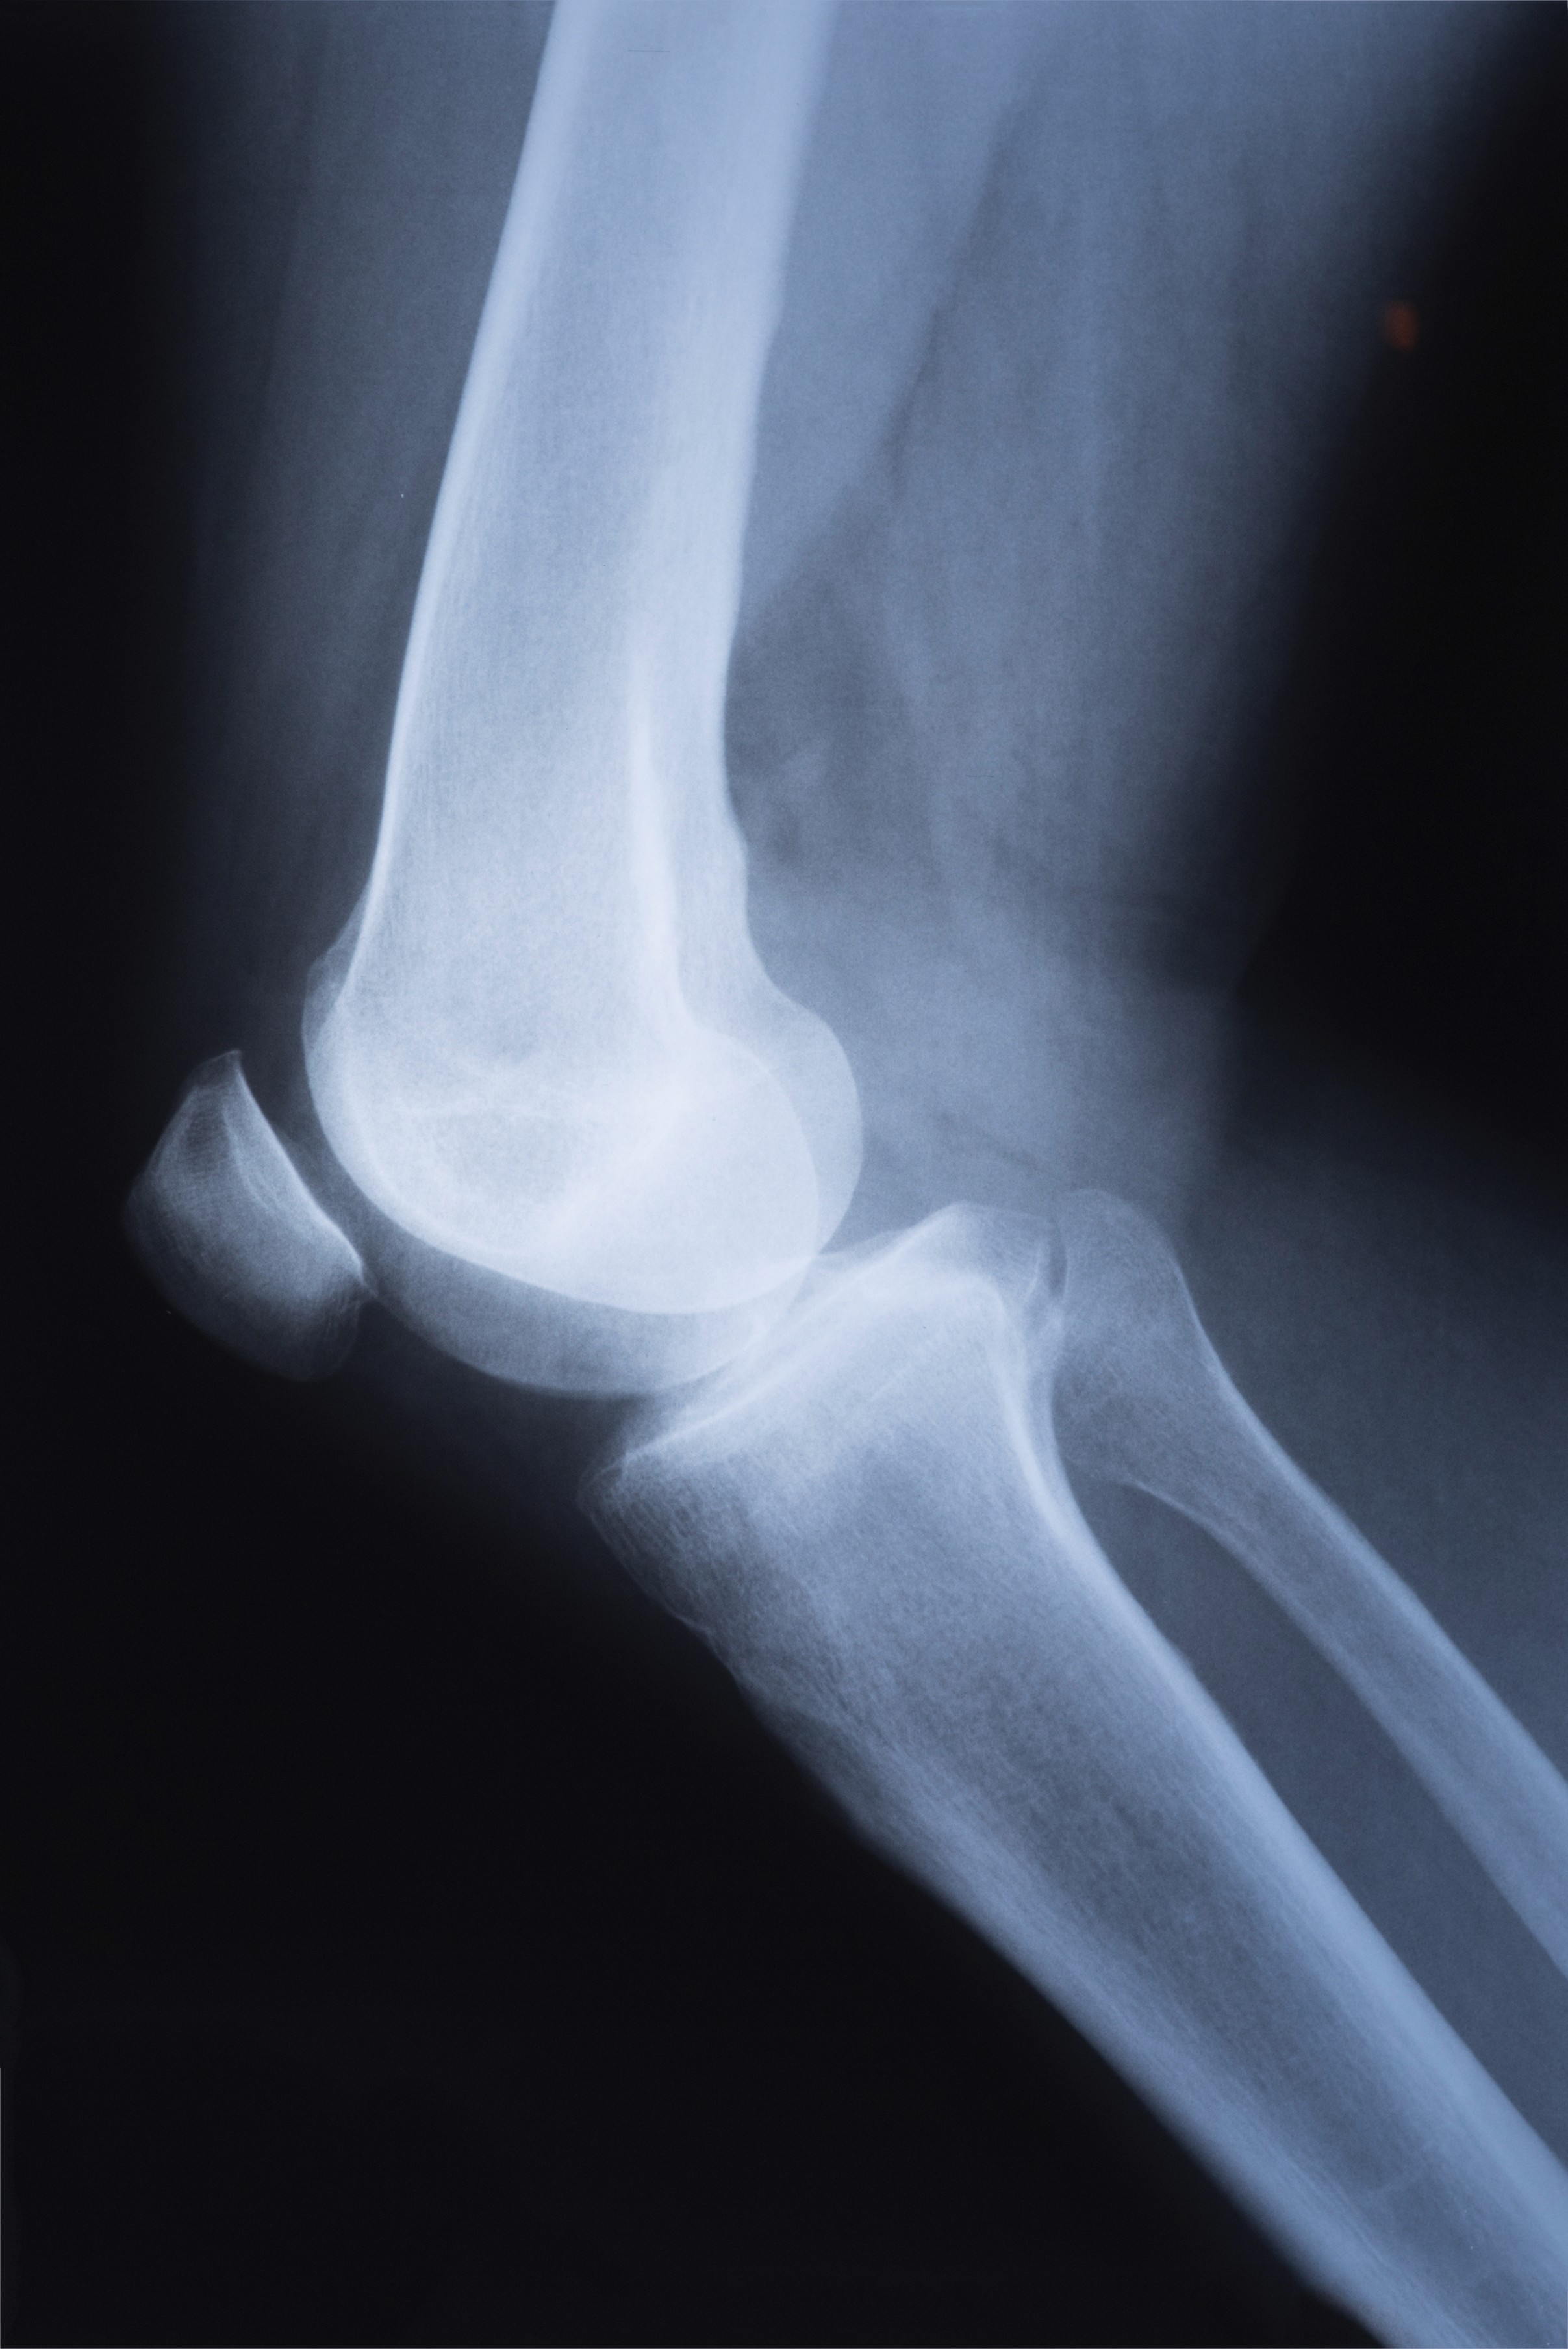

Atendemos pacientes com dores articulares, limitações físicas e dificuldades de movimento, oferecendo tratamentos para promover recuperação segura e melhorar a autonomia no dia a dia.

Todo paciente passa por uma avaliação para entender suas dores, limitações e histórico de saúde. A partir disso, desenvolvemos um plano terapêutico focado na recuperação funcional, melhora da mobilidade e prevenção.